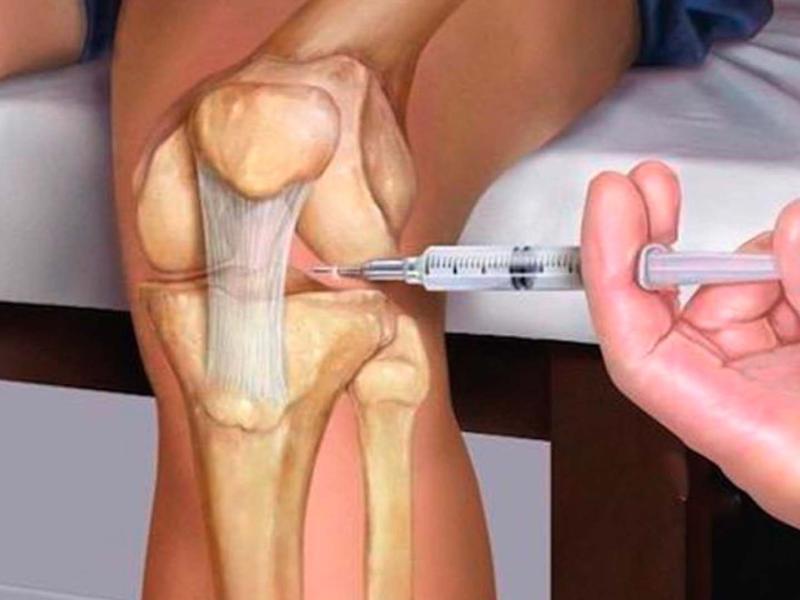

خطوات حقن الركبة والمفاصل بالدهون

حقن الدهون في الركبة من الإجراءات التي قد تتم في وقت قصير نسبيًا مقارنة ببعض الجراحات، لكن هذا لا يعني أنه إجراء بسيط لكل الحالات؛ فهو يحتاج إلى تعقيم جيد، تقييم دقيق، وخبرة في تحديد الحالة المناسبة وطريقة الحقن.

وتتمثل الخطوات في:

- في البداية يقوم الطبيب بسحب كمية مناسبة من الدهون، وغالبًا من منطقة البطن، وذلك عن طريق فتحة صغيرة. وفي بعض الحالات لا تحتاج الفتحة إلى غرز، ويكتفي الطبيب بوضع لاصقة طبية أو رباط حسب الحالة.

- ثم يقوم الطبيب بمعالجة هذه الدهون بطريقة خاصة وتجهيزها للحقن.

- ثم يتم حقن الدهون في المفصل المصاب بعد تجهيز المنطقة وتعقيمها.

- بعد ذلك يمكن للمريض اتباع تعليمات الطبيب بخصوص إزالة رباط البطن أو العناية بمكان سحب الدهون.

- يمكن للمريض العودة إلى أنشطته اليومية تدريجيًا، مع تجنب الضغط الزائد على الركبة أو المفصل المصاب في البداية.

- تختلف فترة التعافي من مريض لآخر حسب الحالة ودرجة الخشونة وطريقة الاستجابة للعلاج.